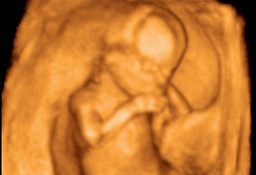

Ecografía de la semana 12

Los motivos por los que los ginecólogos recomiendan realizar una ecografía en la semana 12 de embarazo tienen que ver con el desarrollo anatómico y el tamaño del feto: ahora es lo bastante grande para comprobar si presenta anomalías. Además, ya se puede ver con claridad si hay uno o dos (o tres) bebés, calcular  la fecha probable de parto teniendo en cuenta la edad gestacional, y confirmar que esta coincide con el desarrollo del bebé. Se puede medir el llamado pliegue nucal (si sobrepasa unos parámetros a veces es indicio de problemas cromosómicos) y, si el bebé se deja, conocer su sexo.